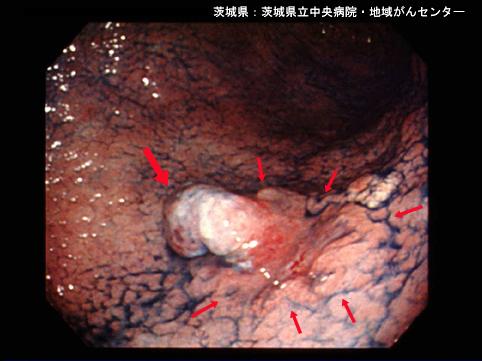

Posted by: Ibaraki Pref., Ibaraki Prefectural Central Hospital & Cancer Center (Ibaraki Prefectural Central Hospital & Cancer Center)

clasificación del pacienteTumor Epitelial Maligno/Adenocarcinoma

parte(separada por órganos)estómago(región)/ángulo

método de exámenEndoscopia

clasificación ectoscópica de tumoresTipo 0(tipo superficial)/Otros

diámetro mayor del tumor20 - 24

grado de penetraciónsm